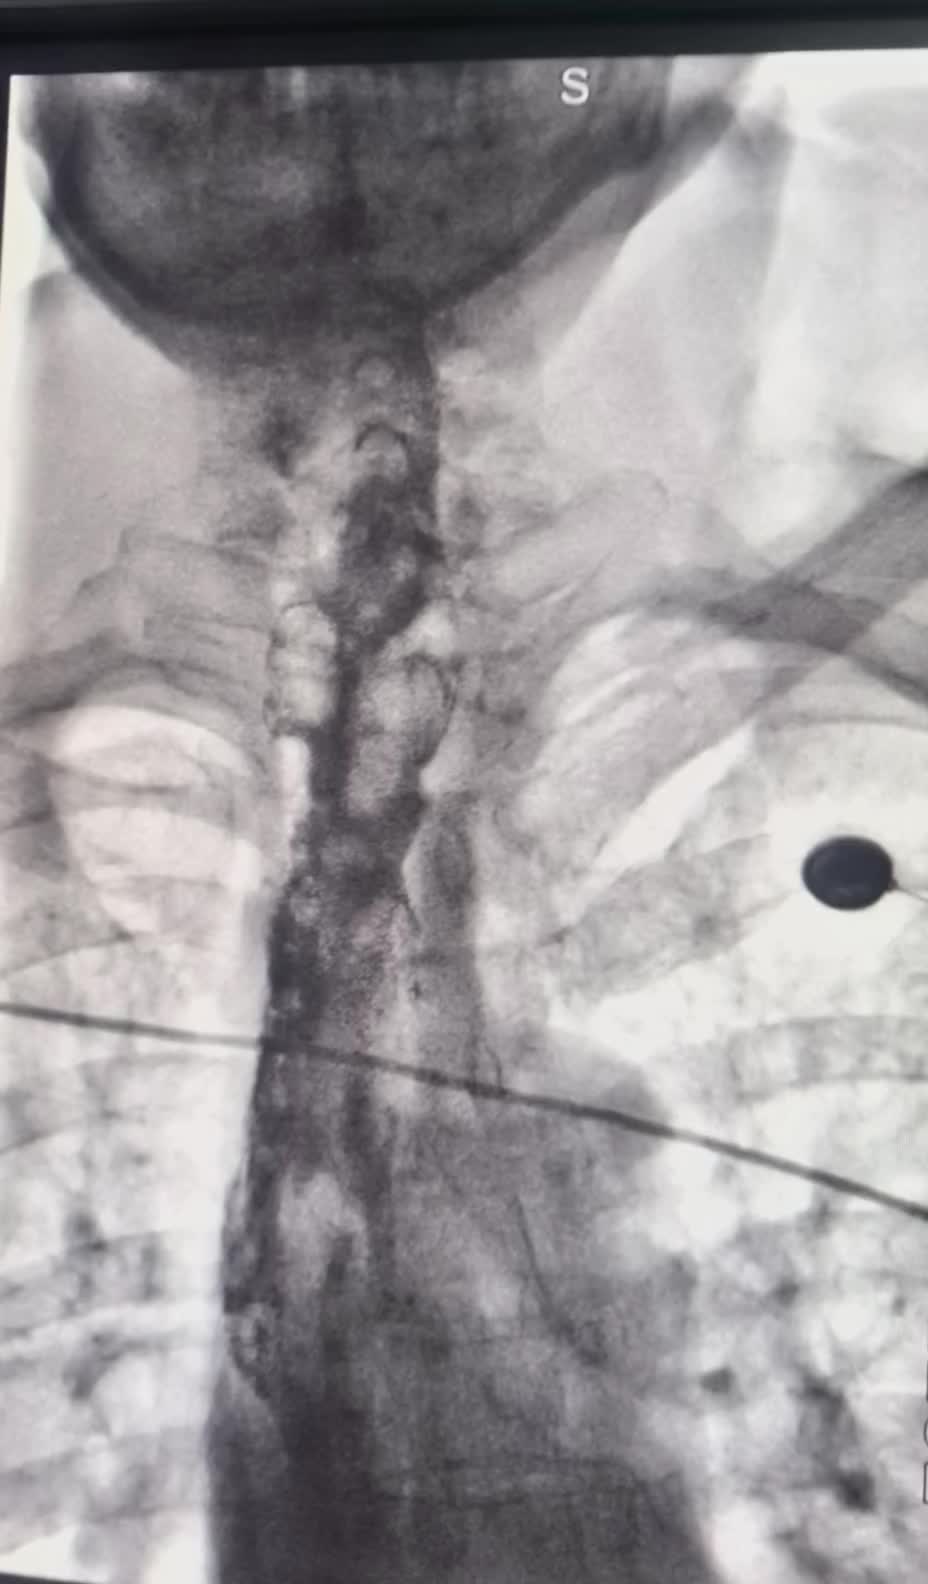

上午一台食管癌术后吻合口狭窄球囊扩张成型 上午一台食管癌术后吻合口狭窄球囊扩张成型术。术后即可恢复正常饮食。